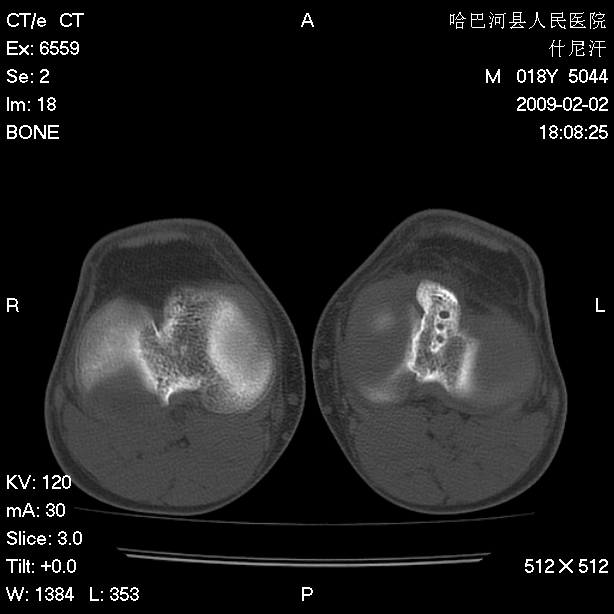

标题: CT17889:外伤后右膝关节反复疼痛3年余 [打印本页]

标题: CT17889:外伤后右膝关节反复疼痛3年余

ct未见明显异常。关节腔未见明显积液,半月板未见明显撕裂。但最好还是mri看看韧带及半月板情况。